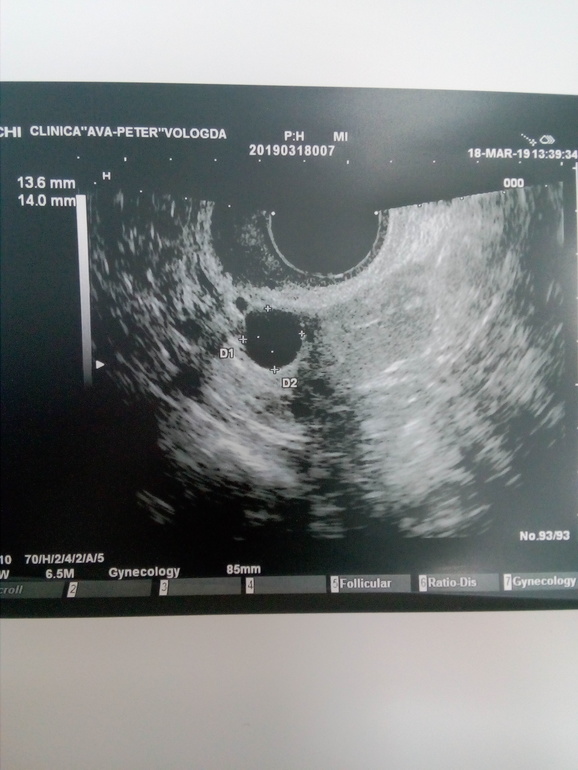

Здравствуйте девушки. Ситуация следующая. Идет первый цикл стимуляции клостилбегит по 1 таб в день со 2 по 6 дц. Врач сказала что перед приемом узи делать не надо, первое через пару дней после последней таблетки. Сегодня пошла на узи и пипец... На левом яичнике киста 29мм. Видимо с прошлого цикла. ХЗ что делать то теперь??? Можно кто сталкивался с таким.

Фото узи

Была на узи на 13 дц киста уже порядком уменьшилась. Во втором Я ДФ был 24мм, но походу он регресировать начал тк стенки были уже не ровные. Я стимулировалась без укола, вот и О не было. ЖДу начало след цикла и снова на стимуляцию, но теперь то схожу и посмотрю что и как до таблеток еще

Спасибо за ответ. Вот и не знаю что и думать. В принципе думаю вряд ли так фолик быстро вымахал. Я переживаю за то что не начала бы киста еще больше расти. Вот еще смущает что она почему то на узи как то не как киста выглядит, что то уж больно края не ровные

Теперь то буду знать. Я что сейчас делать не знаю. Странно что киста не ушла с М. была киста в первом цикле после лапары и ушла после М. И как то уж она выглядит странно, края не ровные какие то.